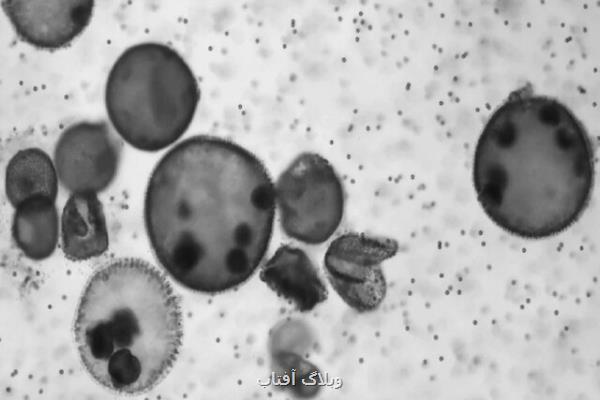

گروه دمیرچی، میکروربات های بیوهیبریدی خودرا با بهره گیری از "جلبک های غلتان" یا "ولوُکس"(Volvox) طراحی کردند که به عنوان موتور عمل می کنند. در انتخاب نام ولبات ها از نام این جلبک ها وام گرفته شده است. جلبک های غلتان می توانند بوسیله حرکت همزمان هزاران برآمدگی مو مانند به نام "تاژک"(flagella) شنا کنند که روی سطح آنها قرار دارند.

دمیرچی اظهار داشت: ولوُکس خاصیت های دیگری نیز دارد؛ مانند توانایی حسی ذاتی که آنرا قادر می سازد تا به سمت منبع نور برود و همچنین، توانایی تولید اکسیژن بوسیله فتوسنتز.

ولوُکس مانند سایر جلبک ها، از کلروفیل برای جذب انرژی از نور استفاده می نماید. ولوُکس ها، فعالیت فتوسنتزی و تولید اکسیژن بالاتری را هنگام قرار گرفتن در معرض نور قرمز نشان می دهند. به همین دلیل، گروه دمیرچی از آن برای تنظیم غلظت اکسیژن تولید شده توسط جلبک ها در سلول های تومور استفاده کردند.